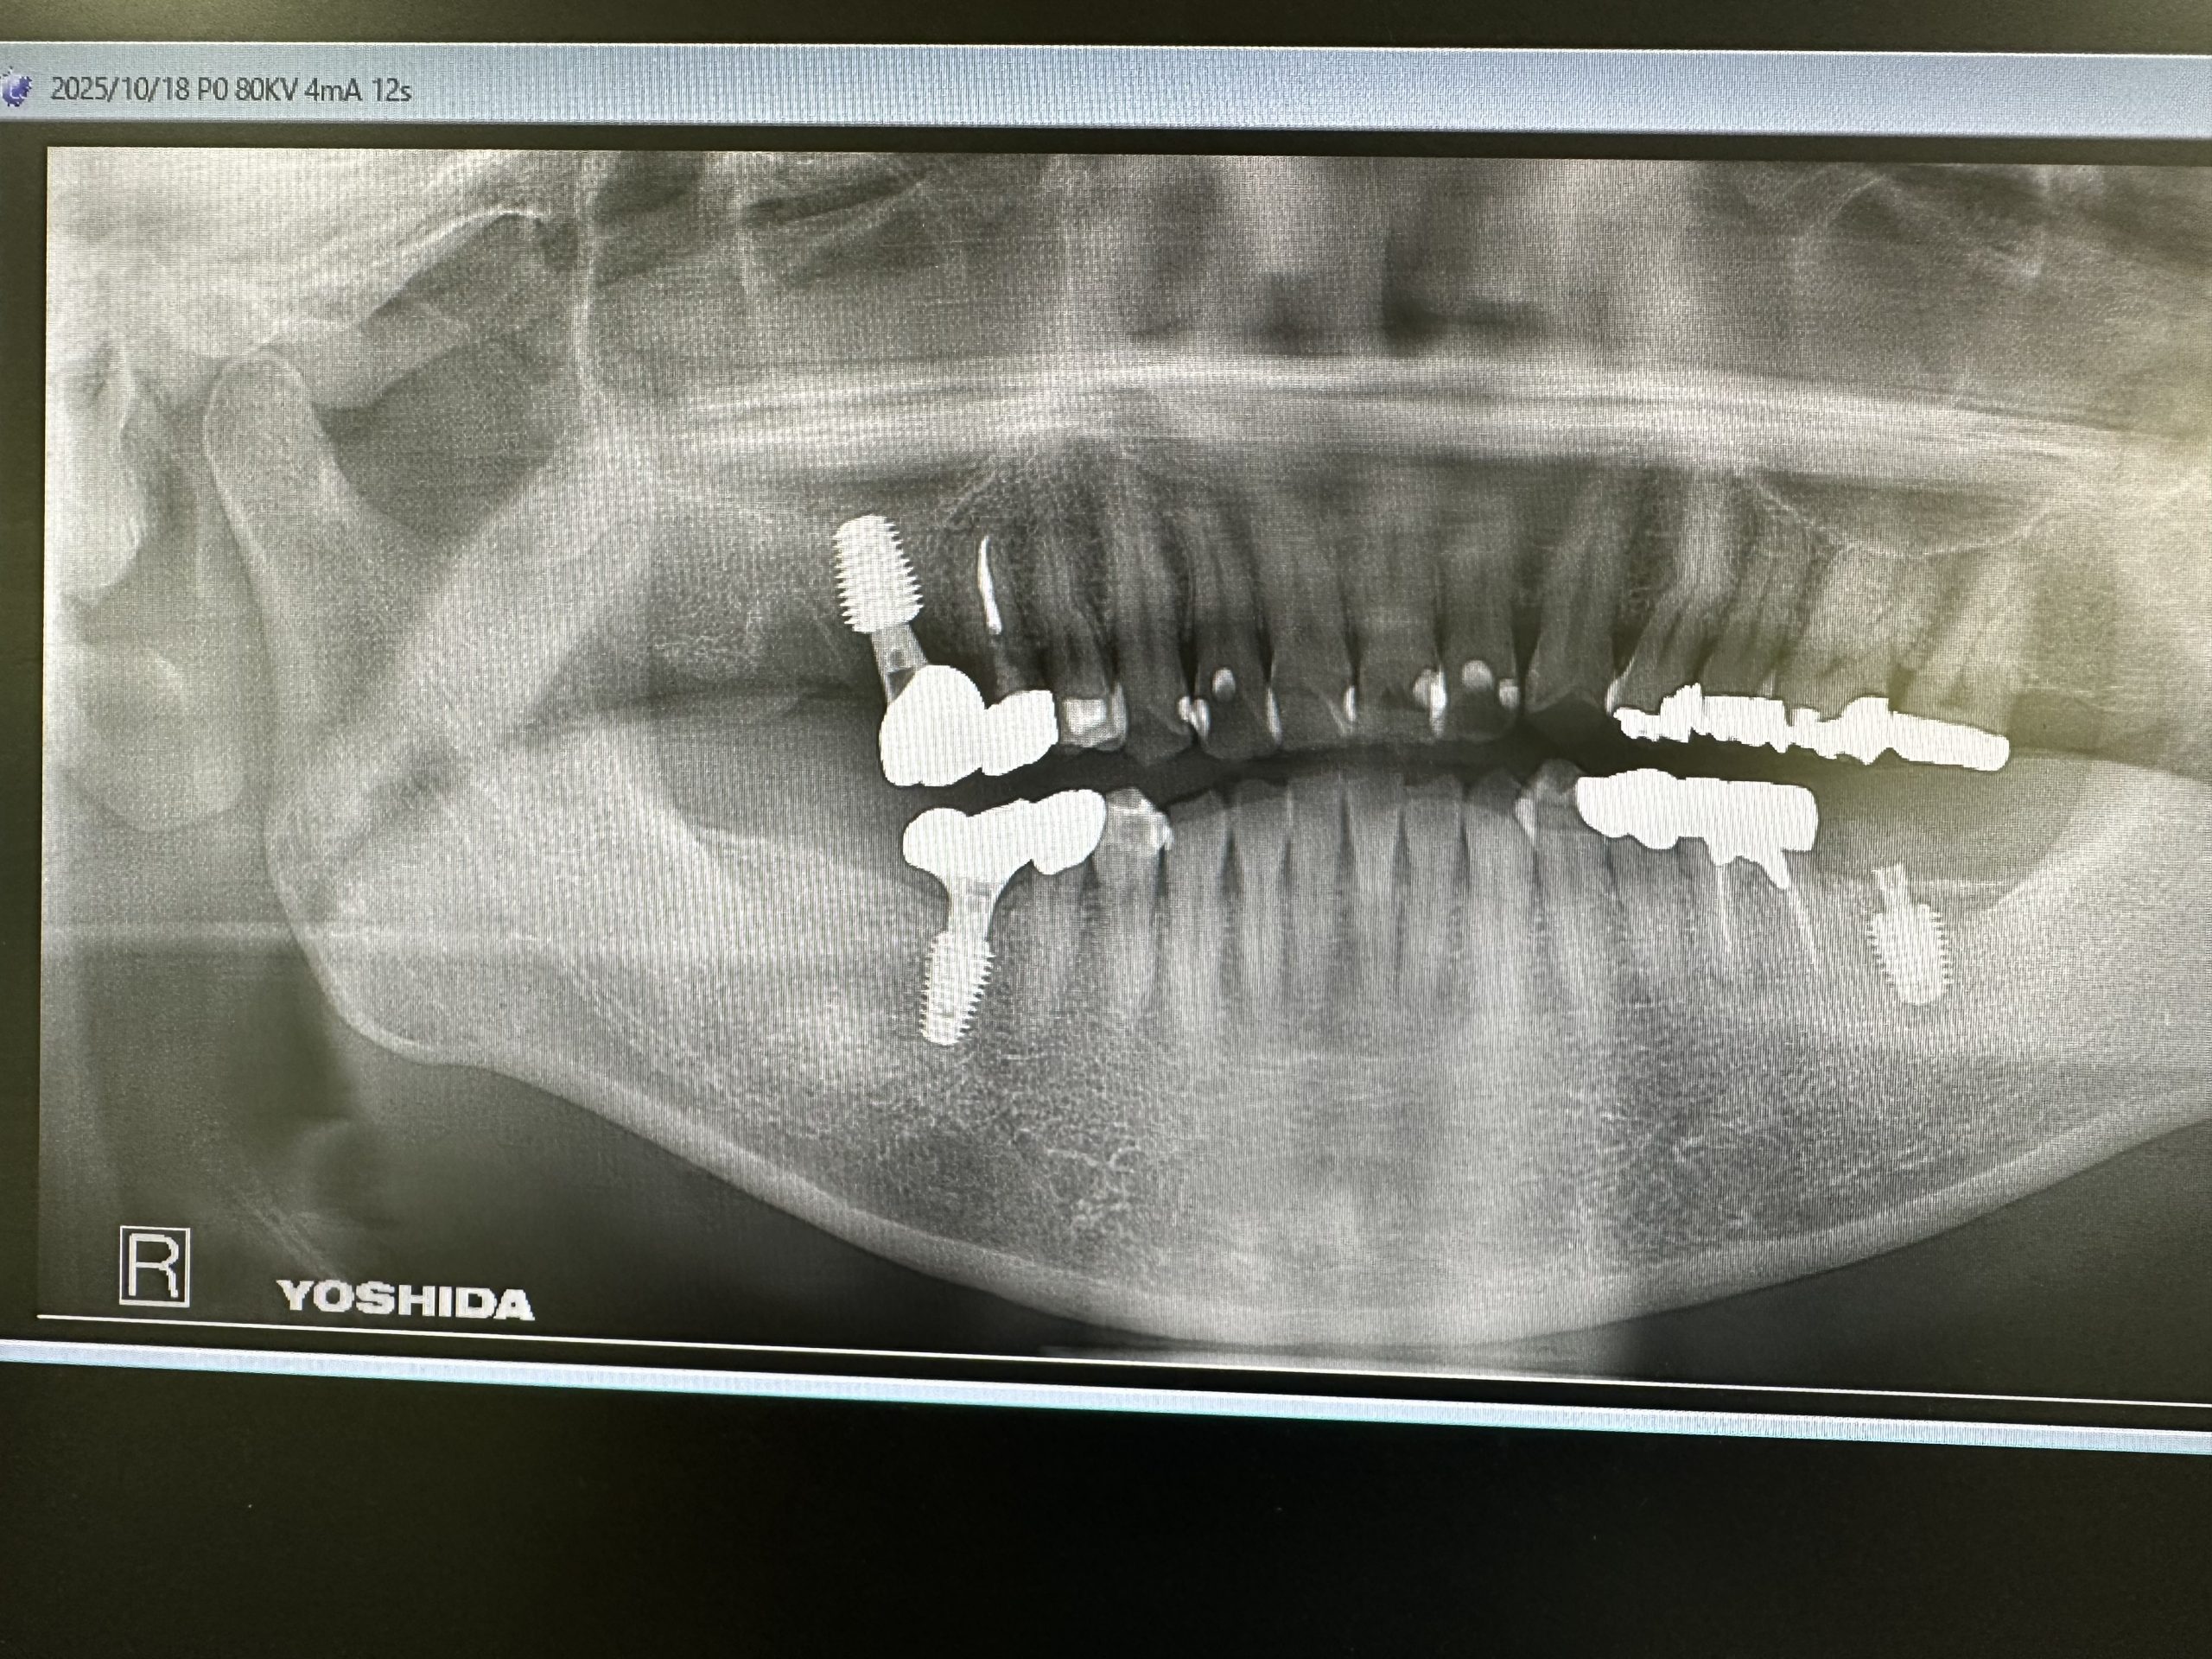

土曜日、本日は2件オペ

御二方共に一本のみ、抜歯即時に成熟埋入

結果20分から30分で終わり、ストレスなし

計測値も良く6w後には仮歯印象だね